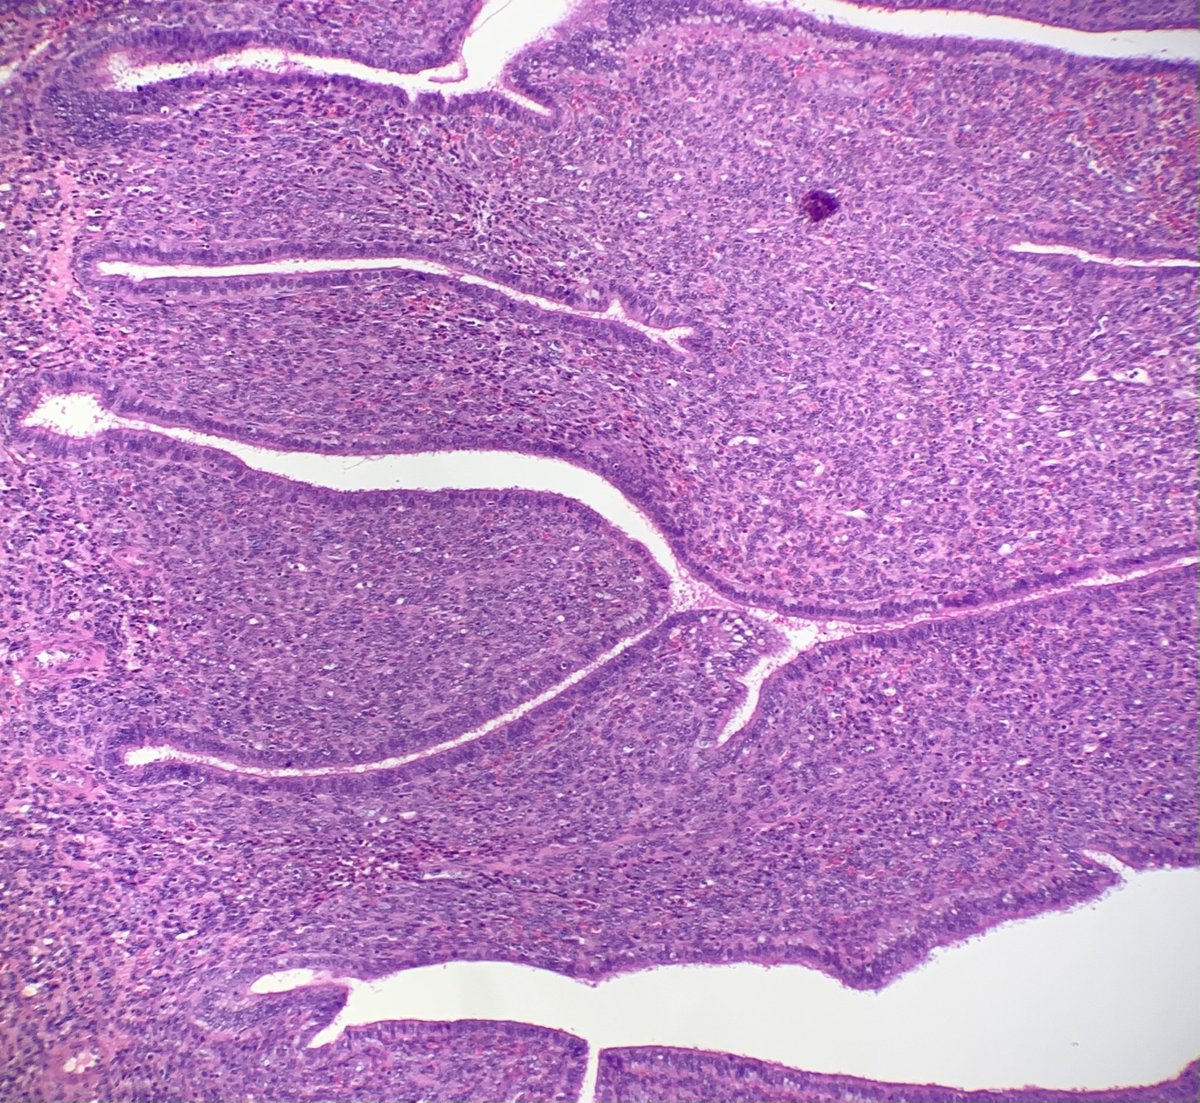

60-year-old man with an incidental mediastinal mass. What is the diagnosis? A) True thymic hyperplasia B) Thymic follicular hyperplasia C) Thymoma ─ Type AB D) Micronodular thymoma with lymphoid stroma #Pathology #PathTwitter